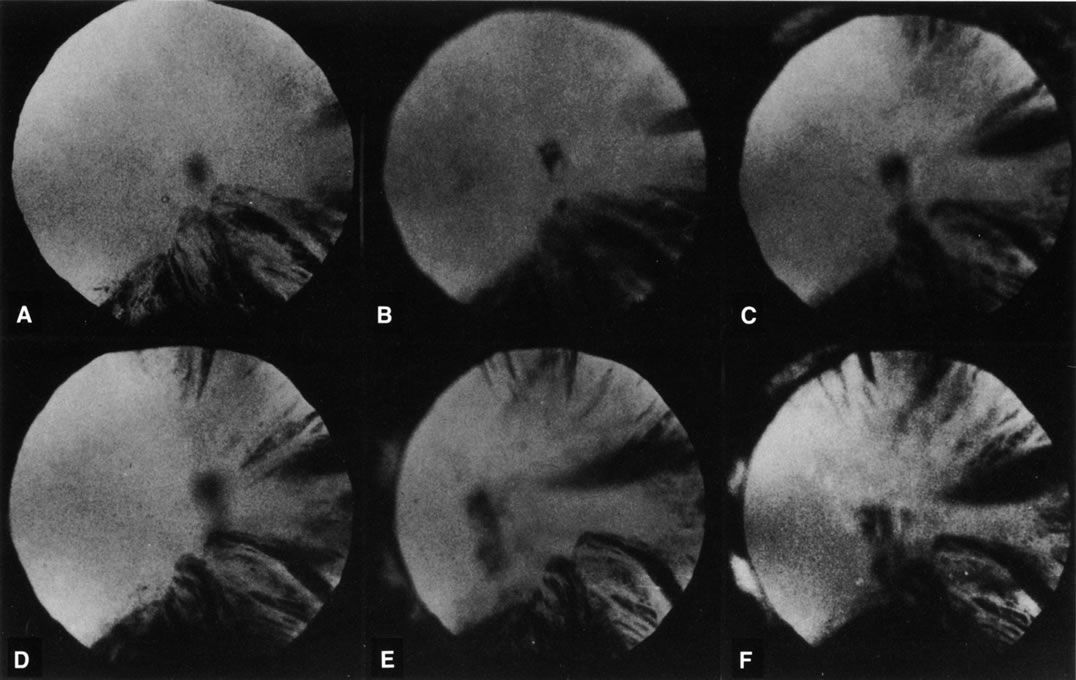

Fig. 8. Follow-up retroillumination photographs of an eye with a cortical cataract, obtained at various intervals. A. First visit (1-21-87); B. 1 year later (1-27-88); C. 22 months later (11-14-88); D. 28 months later (12-4-89); E. 35 months later; F. 41 months later (6-18-90). With such photographs one may be able to plot the progression rate of a cortical cataract, and aid in performing longitudinal studies. Note the central opacity, which is out of focus and represents a small posterior subcapsular cataract.